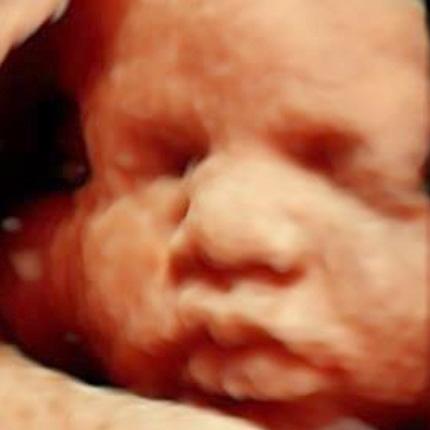

WOMEN’S HEALTH AT ALL STAGES OF LIFE.

Our OB-GYN team specializes in women’s health — caring for you during all stages of life. From Pap testing and contraceptive counseling to pregnancy care and menopausal concerns, you can get exactly the care you need right in Faribault, Mankato and Owatonna.